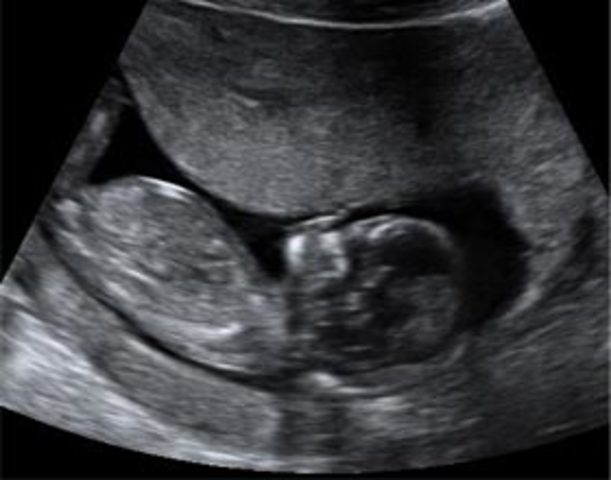

El embrión mide entre 2 y 3 centímetros, su forma ya es mucho mas parecida a un ser humano. Las piernas se alargan, aparecen las manos,, se observa el tuberculo genital que va a denterminar los genitales femeninos o masculinos.

Los genitales externos se distinguen con claridad, esta terminando la etapa embrionarioa y muy pronto pasará a la fetal